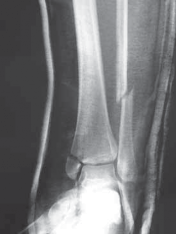

A B C FIG 3•

Radiographic evaluation with an ankle trauma series: AP (

A

), lateral (

B

), and mortise (

C

) views.